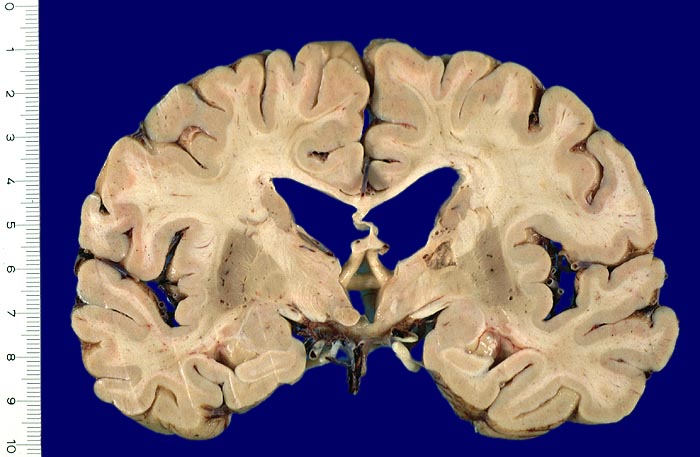

Unregelmässig begrenzter Hohlraum (lakunärer Infarkt) im Bereich der Capsula interna. Die Seitenventrikel sind erweitert.

Lakunäre Infarkte im Bereich des Linsenkerns, des Thalamus, der Capsula interna, der tiefen weissen Substanz, des Nucleus caudatus und der Pons sind weniger als 1.5cm gross und oft Folge einer hypertensiven Enzephalopathie (Atherosklerose der Arteriolen, welche Basalganglien, weisse Substanz und Hirnstamm versorgen). Das Vorliegen multipler Lakunen wird als Status lacunaris bezeichnet. Die Infarkte sind je nach Lokalisation symptomatisch oder asymptomatisch.